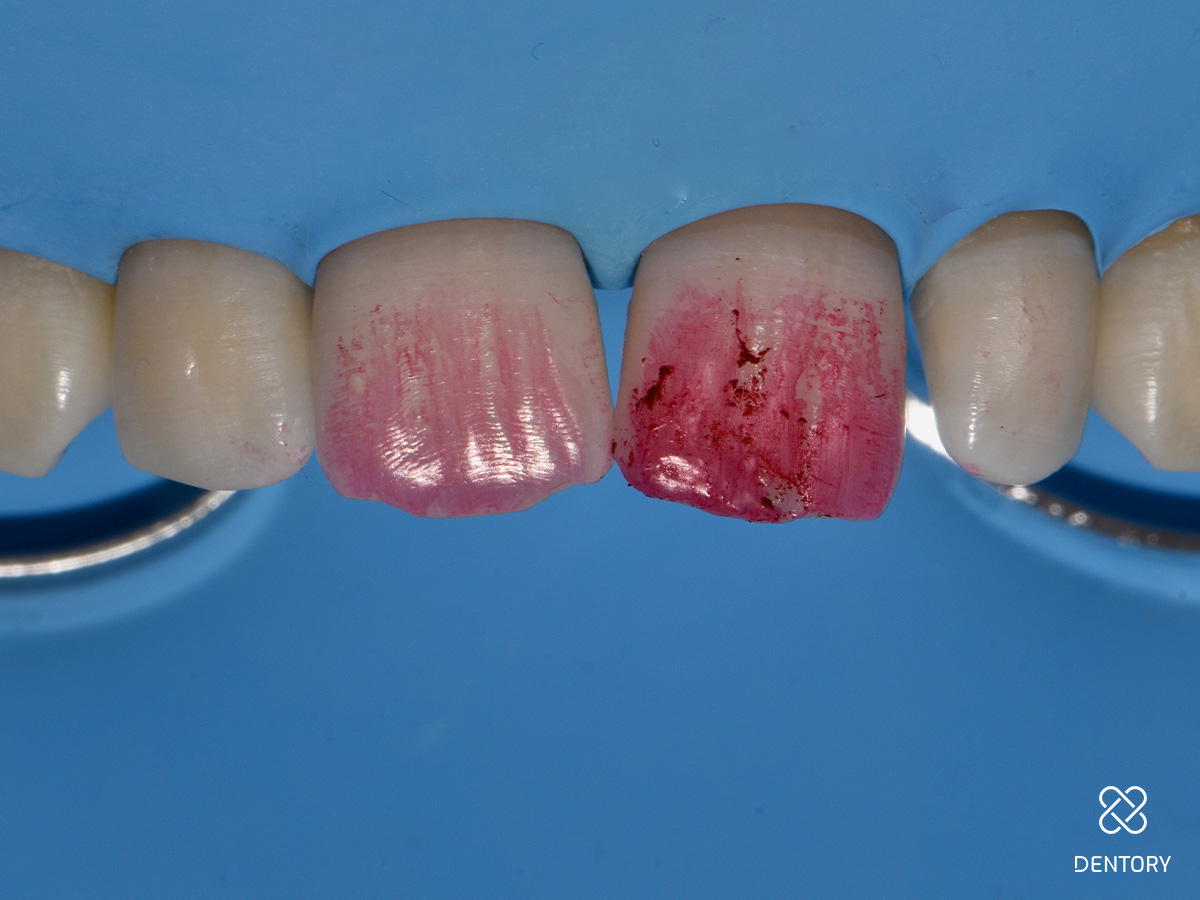

Abbildung 3

Eine breite, wellenförmig verlaufende Anschrägung sorgt für einen fließenden Übergang zwischen Zahn und Restauration hinsichtlich Form und Farbe. Scharfe Kanten und Ecken sollten abgerundet werden.